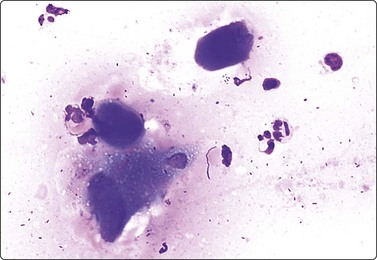

image image

Fig. 14.13 Squamous cell carcinoma

(A) Aggregate of pleomorphic, obviously malignant cells with dense squamoid cytoplasm and distinct cell borders; no obvious keratinization in this field; FNB smear from ulcerated 10–15-mm tumor lower lip (MGG, HP); (B) Cohesive tissue fragment of malignant squamous epithelial cells; scrape smear from ulcerated skin tumor (Pap, HP).

Cytological criteria of squamous cell carcinoma are described in several other chapters, mainly in Chapter 8. The differential diagnosis between well-differentiated squamous carcinoma with cystic degeneration and branchial and other benign cysts lined by squamous epithelium can cause problems due to subtle squamous cell atypia in the former and reactive atypia and metaplasia in the latter (see Chapter 4). Distinction between keratotic basal cell carcinoma and basaloid squamous cell carcinoma can be difficult.4 Cytological criteria for basal cell carcinoma are listed below. The cytomorphology of adenoid (acantholytic) squamous cell carcinoma can cause problems.44 Distinction between in situ (dysplastic solar keratosis, Bowen’s disease) and superficially invasive carcinoma is not possible in smears.